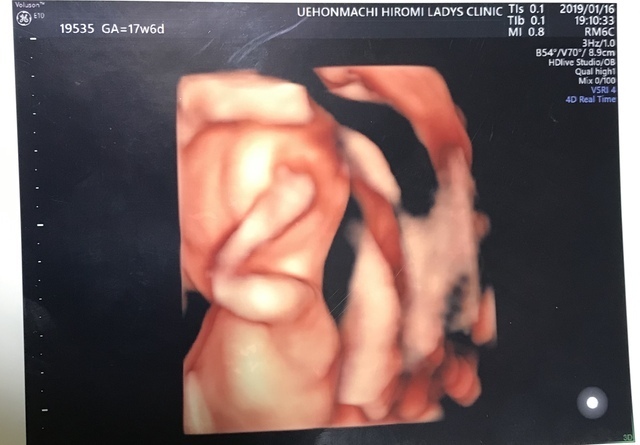

17週4日(17w4d・男の子)|ayu♡ さん(35歳)

エコー写真撮影時のエピソード:

この子の初めての4Dエコーでした。健診が終わって会計待ちの間に、主人にエコーの写メを送りました。

主人は男の子が欲しかったので、ファイティングポーズをしているエコーだったから、男の子に間違いないと!しばらくして主治医からも男の子だろうと言われ、喜んでいた主人を思い出します。